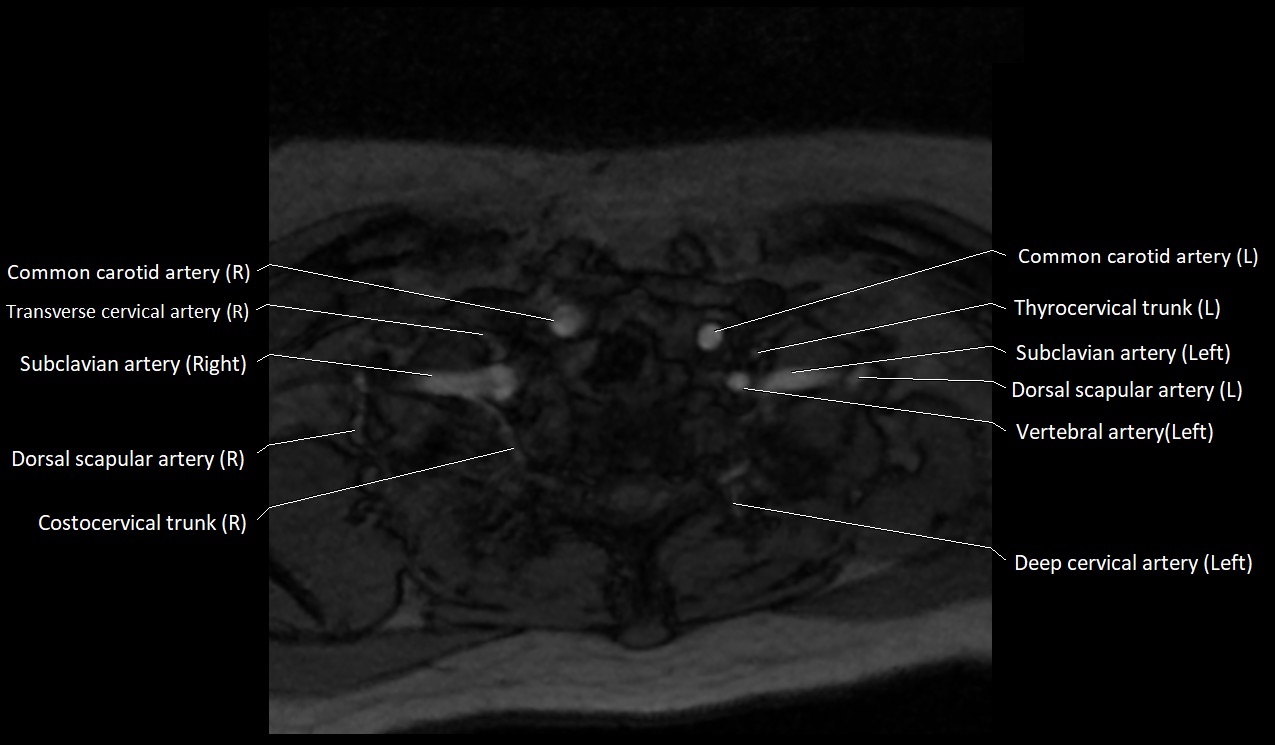

MRI Appearance:

• T1-Weighted Images:

• Appears as a tubular, hypointense (dark) structure relative to muscle

• May show flow void if the blood flow is fast

• T2-Weighted Images:

• Typically hypointense or isointense to muscle, but can be hyperintense if slow flow or stasis is present

MRI images